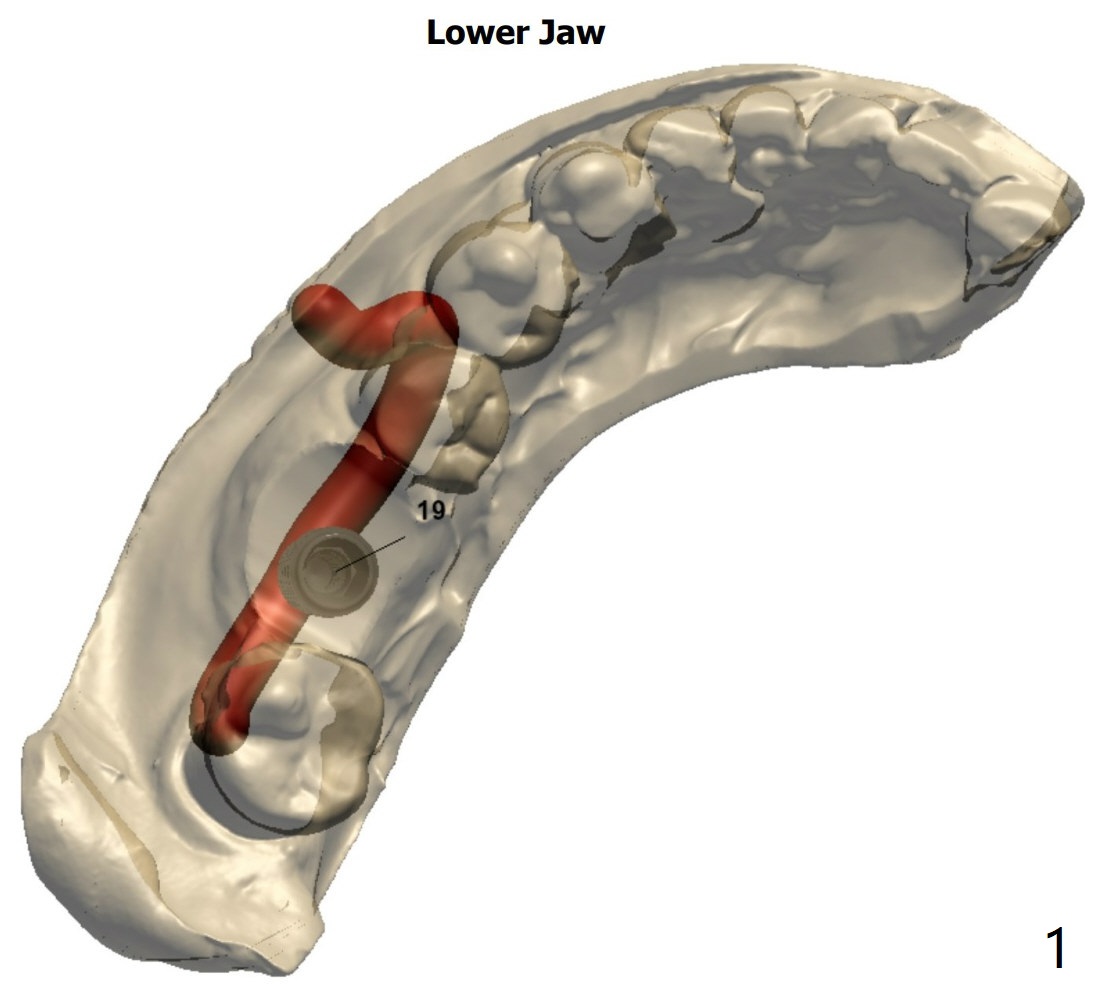

A 59-year-old man has toothache associated with root split of the tooth #19. Due to severe bone loss, a 4.5x8.5 mm implant will be placed in the septum. PRFx1. Remove guide after 3.5x7.3 mm drill or place a 4x10 mm implant to determine whether there is bone buccolingually to hold the 4.5x8.5 mm fixture.